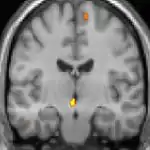

| Voxel-based morphometry (VBM) shows brain area structural differences. | ||

Positron emission tomography (PET) scans indicate the brain areas which are activated during attack only, compared to pain free periods. These pictures show brain areas that are active during pain in yellow/orange color (called "pain matrix"). The area in the center (in all three views) is specifically activated during CH only. The bottom row voxel-based morphometry (VBM) shows structural brain differences between individuals with and without CH; only a portion of the hypothalamus is different.[36]